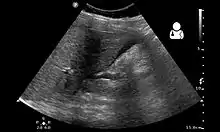

| Ruptured heterotopic pregnancy on ultrasound[1] | |